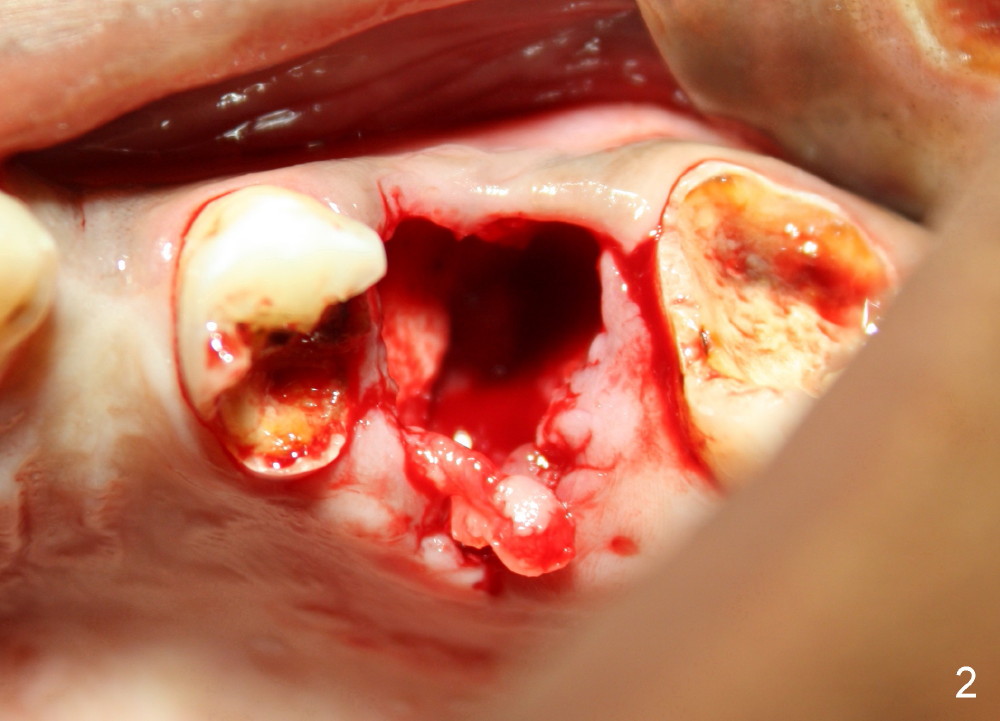

A 24-year-old man has poor dentition. The tooth #14 is beyond salvageable (Fig.1). The extraction socket is large (Fig.2). Dry socket develops 6 days post extraction without socket preservation (Fig.3).